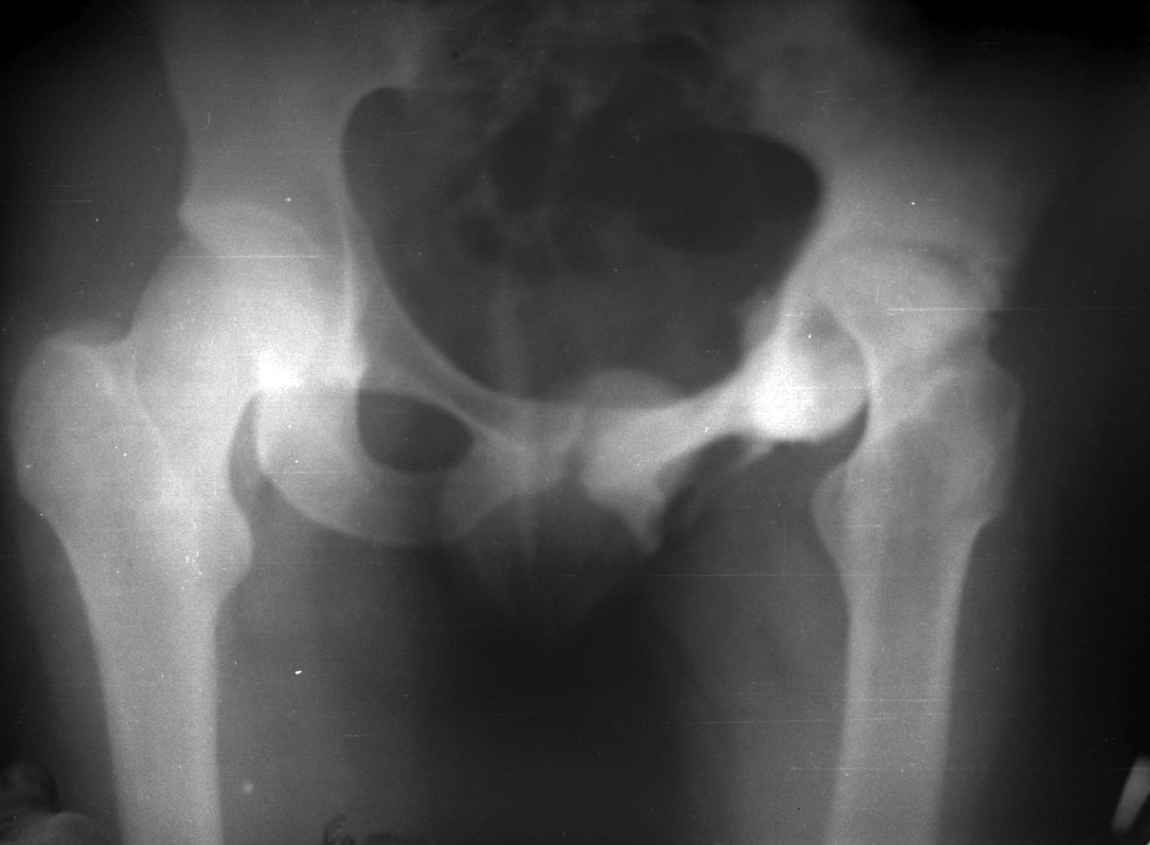

Moghno i tak kak sdelali my: pelvic support + tibial and equinus correction .

Слайд 1

Слайд 2

Слайд 3

Слайд 4

Devushka predstavlennaya na snimke nachala s LLD 9 cm, valgus deformation of the tibia, huge Trendelenburg( vidno na snimke).

Seichas : no LLD ,no Trendelenburg, reasonable hip motion.A samoe glavnoe ei ne predstoit kaghdye 10-15 let delat revision THR.